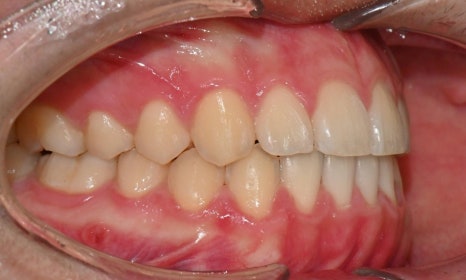

외관상으로는 아랫입술이 돌출되어 보이고 아래 치아가 좌측으로 치우치면서 치아 중심선(midline)이 맞지 않는 상태였습니다. 또한 환자는 어릴 적 넘어지면서 앞니가 깨졌던 외상 병력이 있었고, 그 영향으로 앞니 뿌리가 부분적으로 흡수된 상태였습니다.

2024.12. 초진 구내사진 - 연세정원치과

정밀 검진 결과, 하악 치열이 좌측으로 틀어져 있었고 그로 인해 위아래 치아 중심선이 일치하지 않았습니다. 아래 치열이 전체적으로 전방 위치하여 아래 입술 돌출이 더 도드라져 보이는 상태였습니다. 그리고 상악궁이 하악궁보다 좁아서 앞니 부위 일부 반대로 물리는 치아 교합도 관찰되었습니다. 특히 외상 치아의 경우, 교정력 적용시 추가적인 염증성 치근 흡수 위험이 존재하기 때문에, 치료 중 지속적인 관찰이 필수적인 상황이었습니다.

치료 시작 7개월 후 사진으로, 치아 배열 후 아래 우측에 미니스크류를 식립하여 치아 중심선을 개선하는 중으로, 교합과 치아 중심선이 많이 개선된 것을 확인할 수 있습니다.

약 1년 간의 교정 치료를 통해 어긋나 있던 치아 중심선이 자연스럽게 맞춰졌고, 중심선 비대칭이 개선 및 하악 아랫입술 돌출도 눈에 띄게 호전되었습니다. 무엇보다 치료 기간 동안 앞니의 치근 흡수는 추가적인 진행 없이 안정적으로 유지되었습니다.

돌출을 조금 더 개선하는 것을 추천했으나, 환자가 갑자기 군 입대를 하게 되어 현 상태로 치료를 마무리하기로 하였습니다. 치료 전후 치아 위아래 중심선이 일치하며 좌우 어금니 교합도 향상되었습니다. 하악 치열의 후방 이동으로 아래 입술의 돌출도도 많이 개선되었습니다. 멀리서도 믿고 내원해주고, 치료 기간 동안 성실히 협조해준 환자분께 감사드리며 앞으로도 건강한 치아로 군 생활 잘 마치길 응원합니다 :)